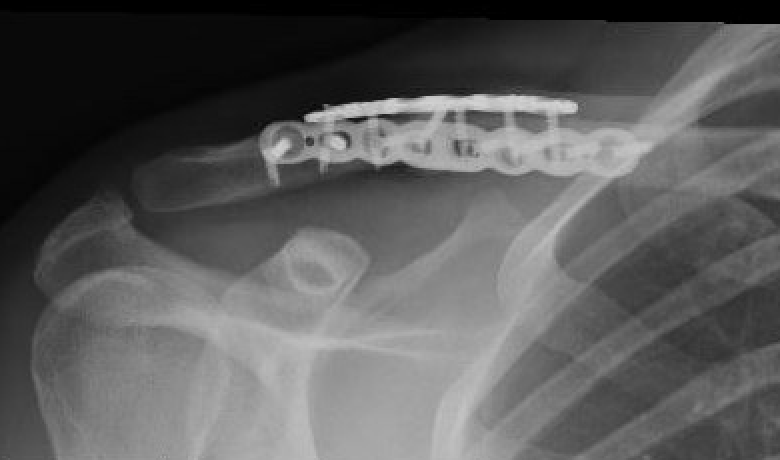

Periprosthetic fracture

Nonunion

Technique

Vumedi dual plating clavicle nonunion

Results

Muhlenfeld et al J Clin Med 2024

- 44 patients with nonunion

- union rate with plate: 94%

- union rate with plate + bone graft: 96%